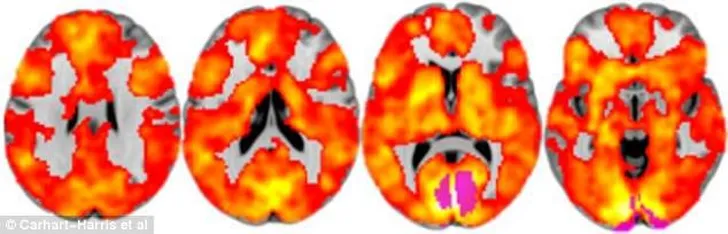

Voor het onderzoek werd de hersenactiviteit van veertig mensen gemeten, waarvan de ene helft echte LSD en de andere helft een placebo kreeg toegediend. Op de scans is zichtbaar dat mensen die hallucineren door de drug daadwerkelijk 'zien' met meerdere delen van hun hersenen. Een soort derde oog, dus, waarmee je bijvoorbeeld geluiden kan zien.

Scans van de mensen onder invloed van LSD

Kinderlijke manier van denken

"Normaal gesproken bestaan onze hersenen uit onafhankelijke netwerken die verantwoordelijk zijn voor aparte en complexe functies. LSD verenigt die verschillende gebieden en laat ze integreren. Dat zorgt voor een veel completer brein. Onze onderzoeksresultaten suggereren dat dit effect ten grondslag ligt aan de extreem veranderende bewustzijnstoestand en hallucinaties. Het verenigde brein is ook gerelateerd aan wat men de ego-oplossing noemt. Tijdens een trip wordt je normale gevoel van eigenwaarde afgebroken en verbind je je opnieuw met jezelf, met anderen en met je omgeving", legt Carhart-Harris uit.